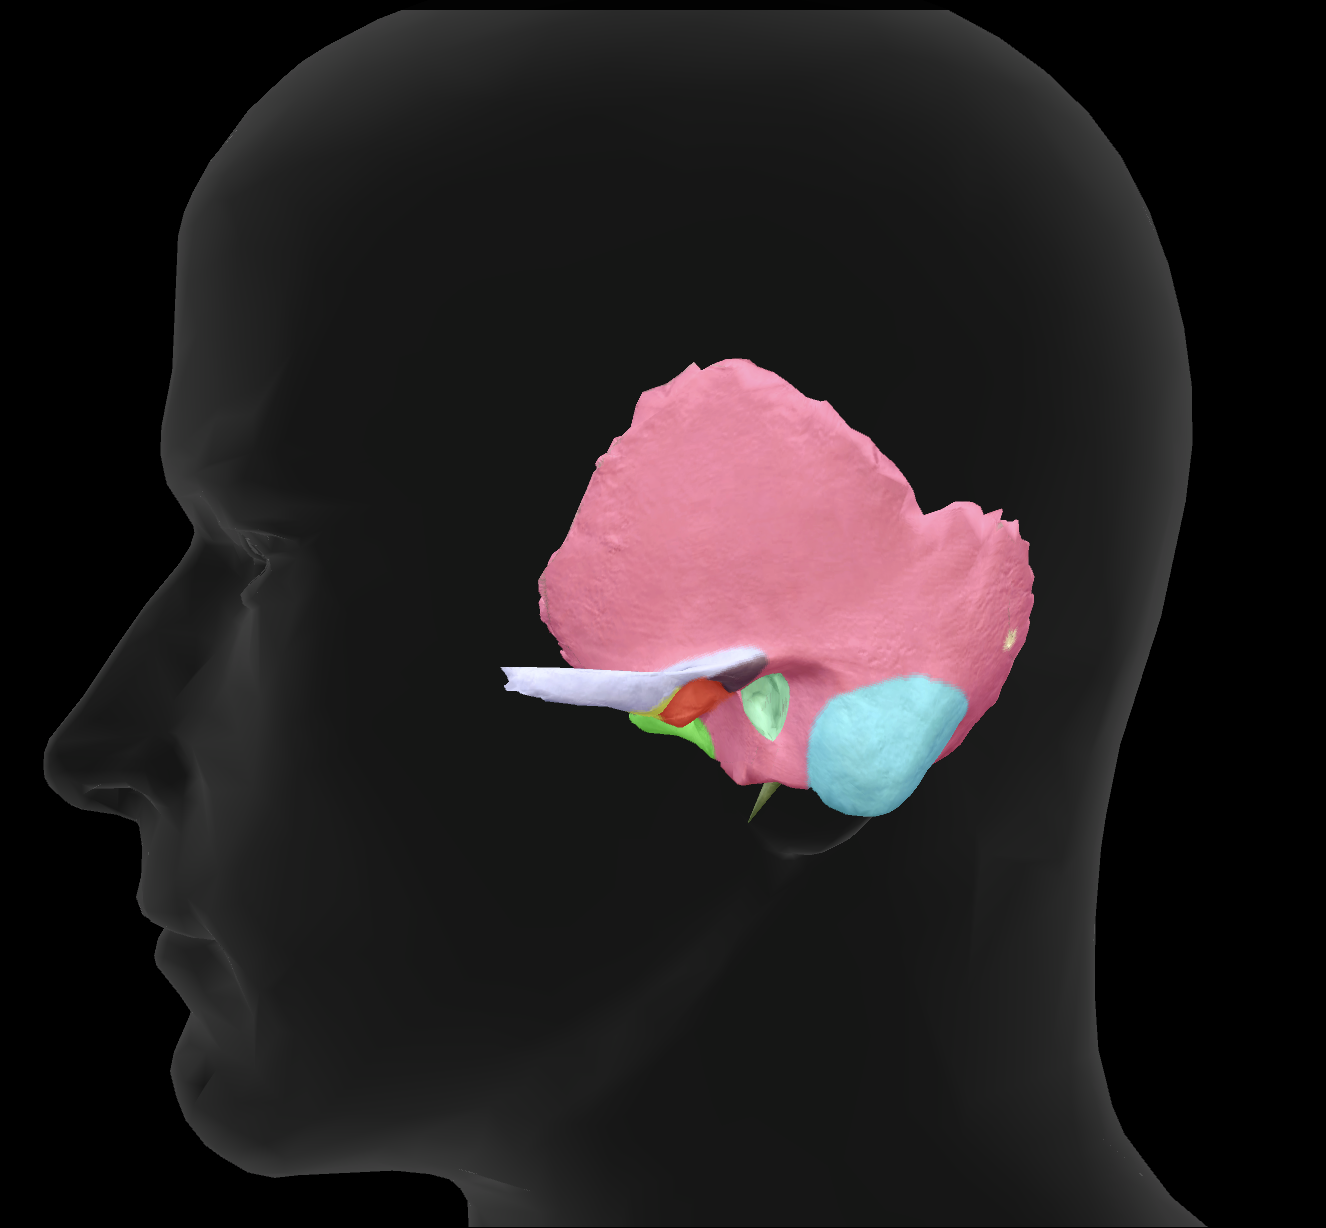

What bone is highlighted?

zygomatic bone

zygomatic process of temporal bone

What is the name of this feature?

external auditory meatus

What is the name of this feature?

mandibular fossa

What is the name of this feature?

mastoid process

What is the name of this feature?

styloid process

What connects to the zygomatic process to make the zygomatic arch?

temporal process of the zygomatic bone